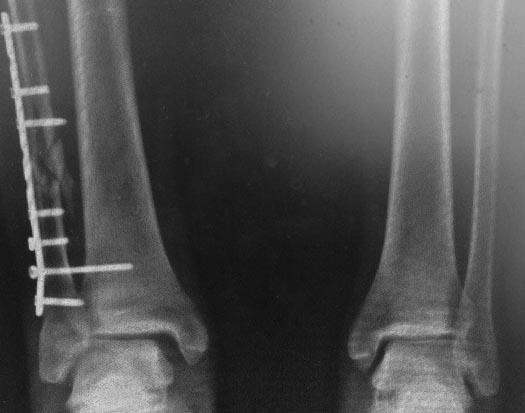

прямая проекция сейчас